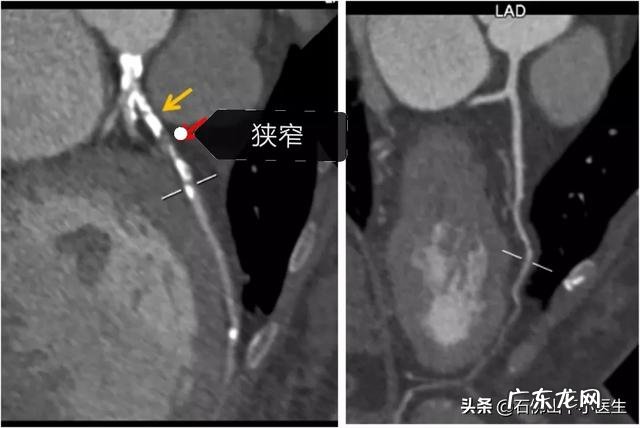

冠脉CT不一定都要检查,可以在患者有症状,查完心电图、心脏超声后,有选择的查 。比如患者活动后胸闷、胸痛,停下来休息会好转,每次发作几分钟时间 。这是典型的稳定性心绞痛的症状 。因为三高的老年人,得冠心病的风险是很高的,如果出现症状,还是需要好好查一查 。总结:老年人合并有三高,是心血管疾病的高危人群,确实应该引起重视 。一方面,好好吃药,控制好血压、血糖、血脂;另一方面,定期做好检查,争取将有些并发症消灭在萌芽里 。当然,zhi疗三高,除了药物之外,生活方式的干预同样很重要 。比如饮食方面、坚持锻炼、保持良好的心态,规律睡眠等等 。我是坚持医学科普的陈大夫,对我回答满意的,请给位点赞和关注 。你的支持,是我创作最大的动力 。